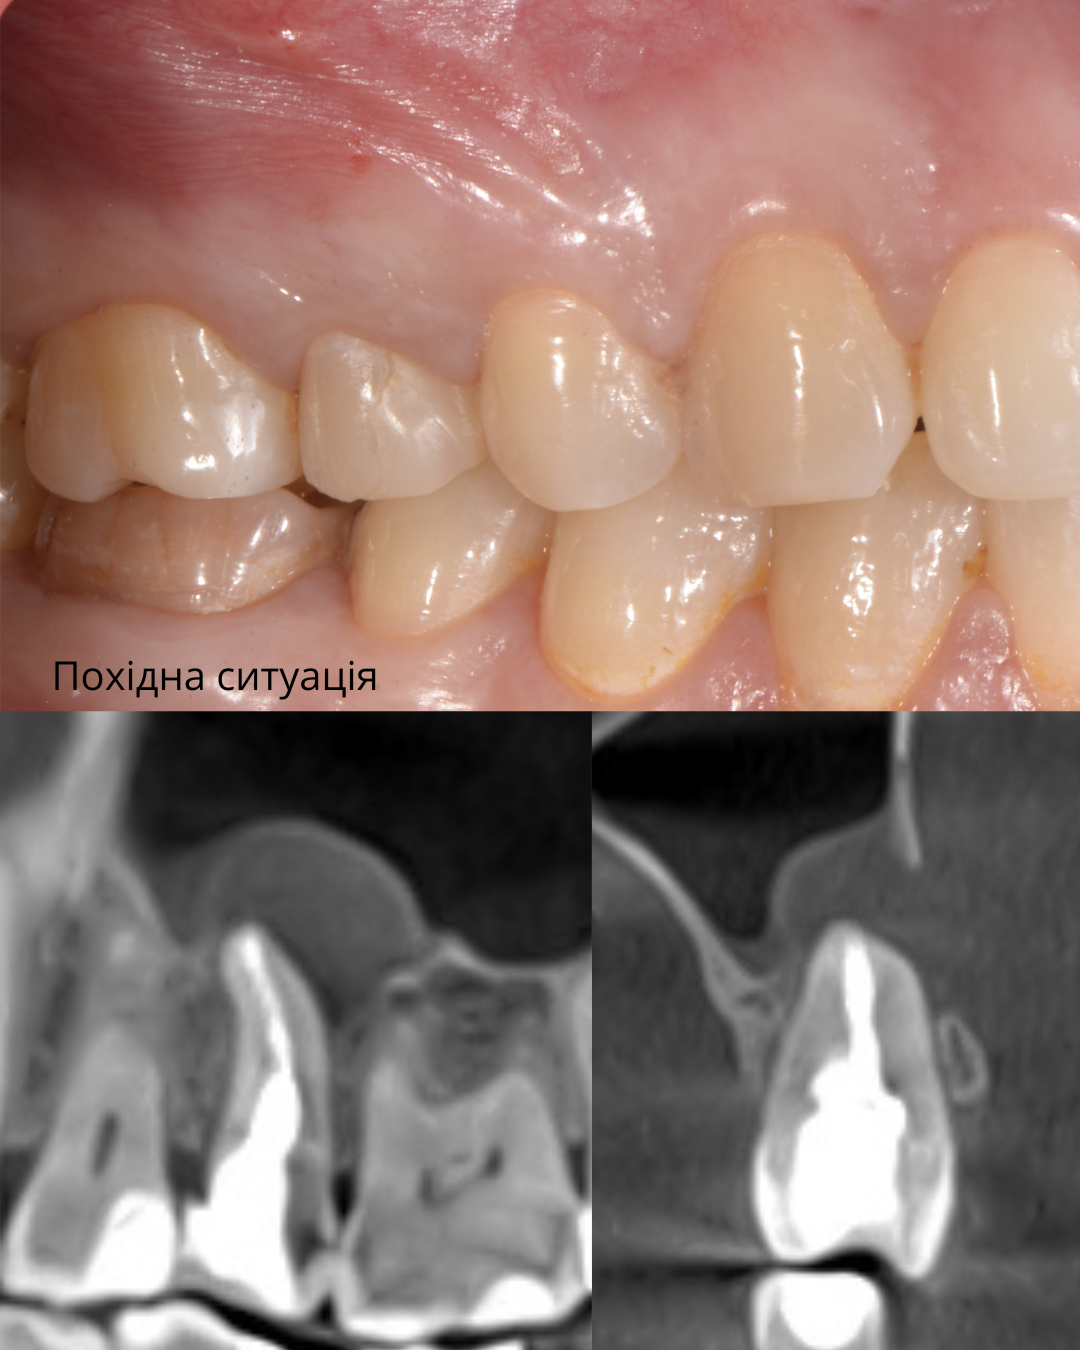

Реабілітація при критичній втраті кісткової тканини

Пацієнт (направлений колегами)

Втрата великої кількості кісткової тканини

Негайна імплантація з тимчасовим протезуванням